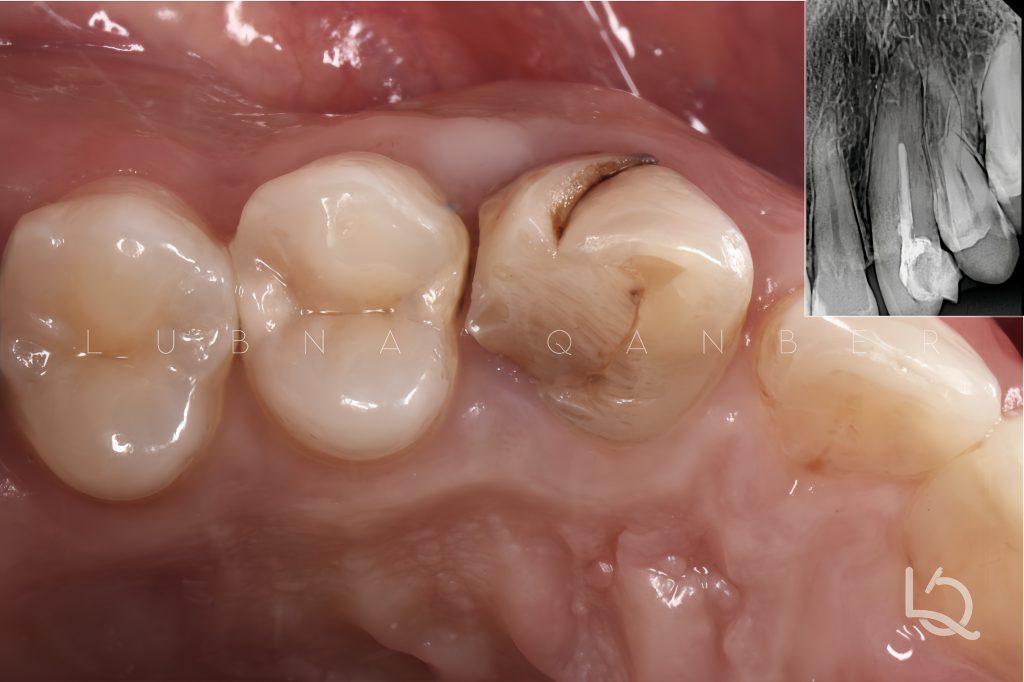

Final finishing and polishing were performed to achieve optimal anatomy and surface texture.

The final radiograph demonstrates a seamless, “infinite” margin on the mesial surface of the premolar and a well-integrated restoration of the canine, with harmonious contours and tight proximal contact.

This case highlights the importance of strategic matrix selection and thoughtful management of proximal contacts, especially in situations where adjacent teeth are carious or compromised and full treatment must be staged over time.

Bioclear matrices, in combination with careful sequencing and stabilization techniques, proved invaluable in achieving biologically sound results.